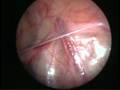

Can this operation done by laparoscopy?

Operation in hernia involves closing of the open passage through which the testis has come down. This can be done from outside as in open surgery or from inside by laparoscopy. If your child has got a hernia on one side, there is a 15 – 25 % chance that he / she may develop a hernia on the opposite side at a later date. With the help of laparoscopy we are able to look at the opposite side to see if the passage is open on that side as well. This can be closed at the same sitting if you wish to. Recovery from surgery, timing of surgery and discharge from hospital are the similar for open surgery and laparoscopic surgery.

However, it is important to note that an open passage does not always mean that your child will get a hernia. There is no harm in opting for a second surgery later if your child at all develops a hernia on the opposite side.

Laparoscopic repairs have a slightly higher chance of recurrence (i.e. the hernia coming back again) as compared to open hernias. You can discuss the pros and cons in details with your doctor when you come for consultation.